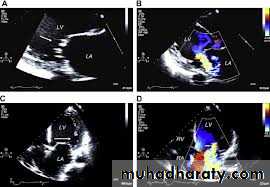

3-Conduction defectC- Echocardiography :

1- LV dilatation2-Mitral and tricuspid regurgitation

3-Reduce ejection fraction -systolic dysfunction

4- Other

$Echo:

important in diagnosis :

1- LV hypertrophy 2- small LV cavity 3- SAM 4-ASH 5-impaired diastolic relaxation

6- mitral regurgitation 7- subaortic gradient if obstructed